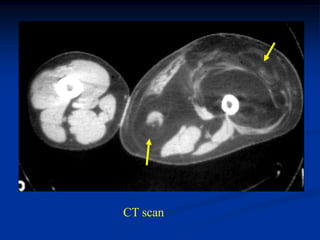

Case #1184.1              Lipoma               CT scan

51 year old male with soft painless mass in buttocks for 5 yrs

Axial T-1     T-2

Gad

Cor T-1         T-2

Sag gad

Case #1184.1 Lipoma CT scan 51 year old male with soft painless mass in buttocks for 5 yrs

• 50.

Axial T-1 T-2 Gad

• 51.

Cor T-1 T-2 Gad

• 52.

• 53.